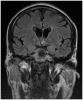

Varón de 44 años natural de Mauritania, sin antecedentes personales relevantes, que consulta por cefalea. La refiere a nivel fronto-temporal bilateral, opresiva, de tres semanas de evolución que asocia náuseas y vómitos en los últimos...

Caso completo | PDF

Neurología: InfecciosasEtiología: Infecciosas / inflamatoria / desmielinizanteDiagnóstico final: Tuberculoma cerebelosoNivel de certeza: